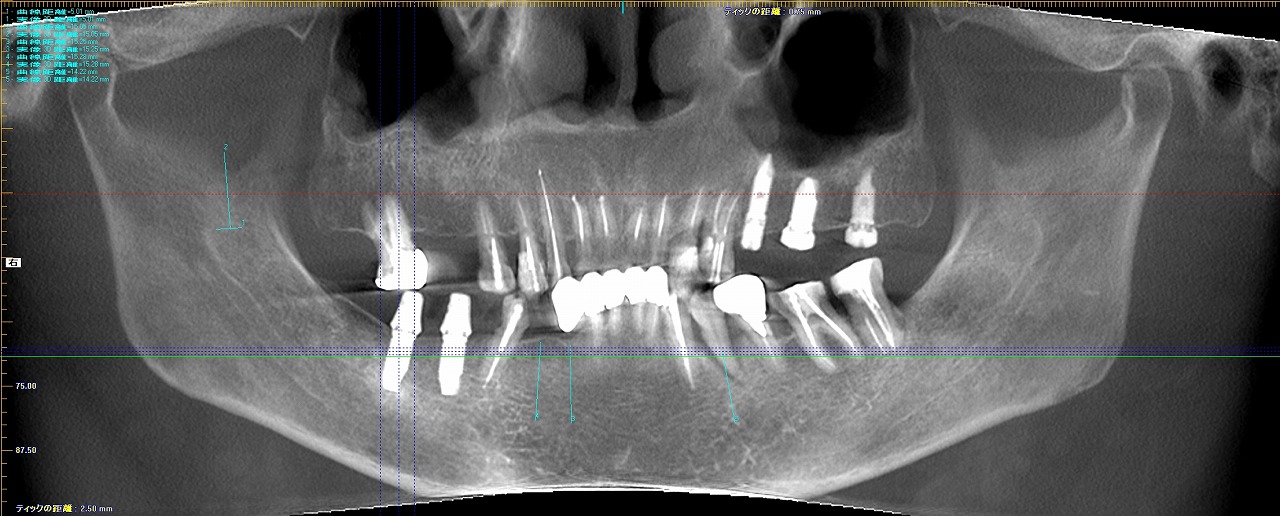

欠損部へインプラントを用いた咬合再構成|お知らせ |広島市安佐南区の歯科医院 欠損部へインプラントを用いた咬合再構成 トップ お知らせ・ブログ お知らせ 欠損部へインプラントを用いた咬合再構成 欠損部へインプラントを用いた咬合再構成 術前のパノラマになります 初診時の口腔内 右側面観 切歯部 左側面観と上顎の咬合面観 下顎の咬合面観 インプラント術後のパノラマになります 大きくすべての歯を仮歯に置き換えていきます 咬合挙上と咬合平面などの修正を加えていきます 部分的に最終補綴に置き換えていきます Web診療予約 初めての方へ 選ばれ続ける理由 院内設備について 歯が痛いしみる一般歯科 歯がぐらぐらする歯周病 健康な歯を保ちたい予防歯科 子供の虫歯予防をしたい小児歯科 銀歯をセラミックに審美歯科 白い歯を目指しませんか?ホワイトニング 矯正専門医がいるので安心矯正歯科 抜けた歯を補いたいインプラント・入れ歯 医院案内 スタッフ紹介 メリィハウス歯科クリニックオフィシャルホームページ ラベンダー歯科クリニックオフィシャルホームページ お知らせ・ブログ ホーム 診療科目 一般歯科 歯周病治療 予防治療 小児歯科 審美治療 ホワイトニング 矯正歯科 入れ歯・インプラント マウスピース矯正 初めての方へ 院長・スタッフ 設備紹介 医院案内・アクセス メニューを閉じる